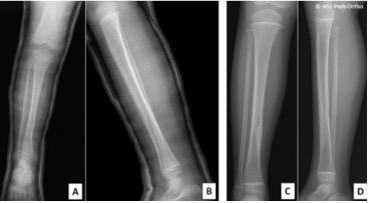

A 10-year-old girl with closed tibial shaft fracture (AO classification: 42D/4.2). (A) Preoperative anteroposterior and lateral radiographs. (B) Immediately postoperative anteroposterior radiographs. (C) 6 months after surgery, tibiofibular synostosis was detected with union. (D) Anteroposterior radiographs 14 months after surgery.